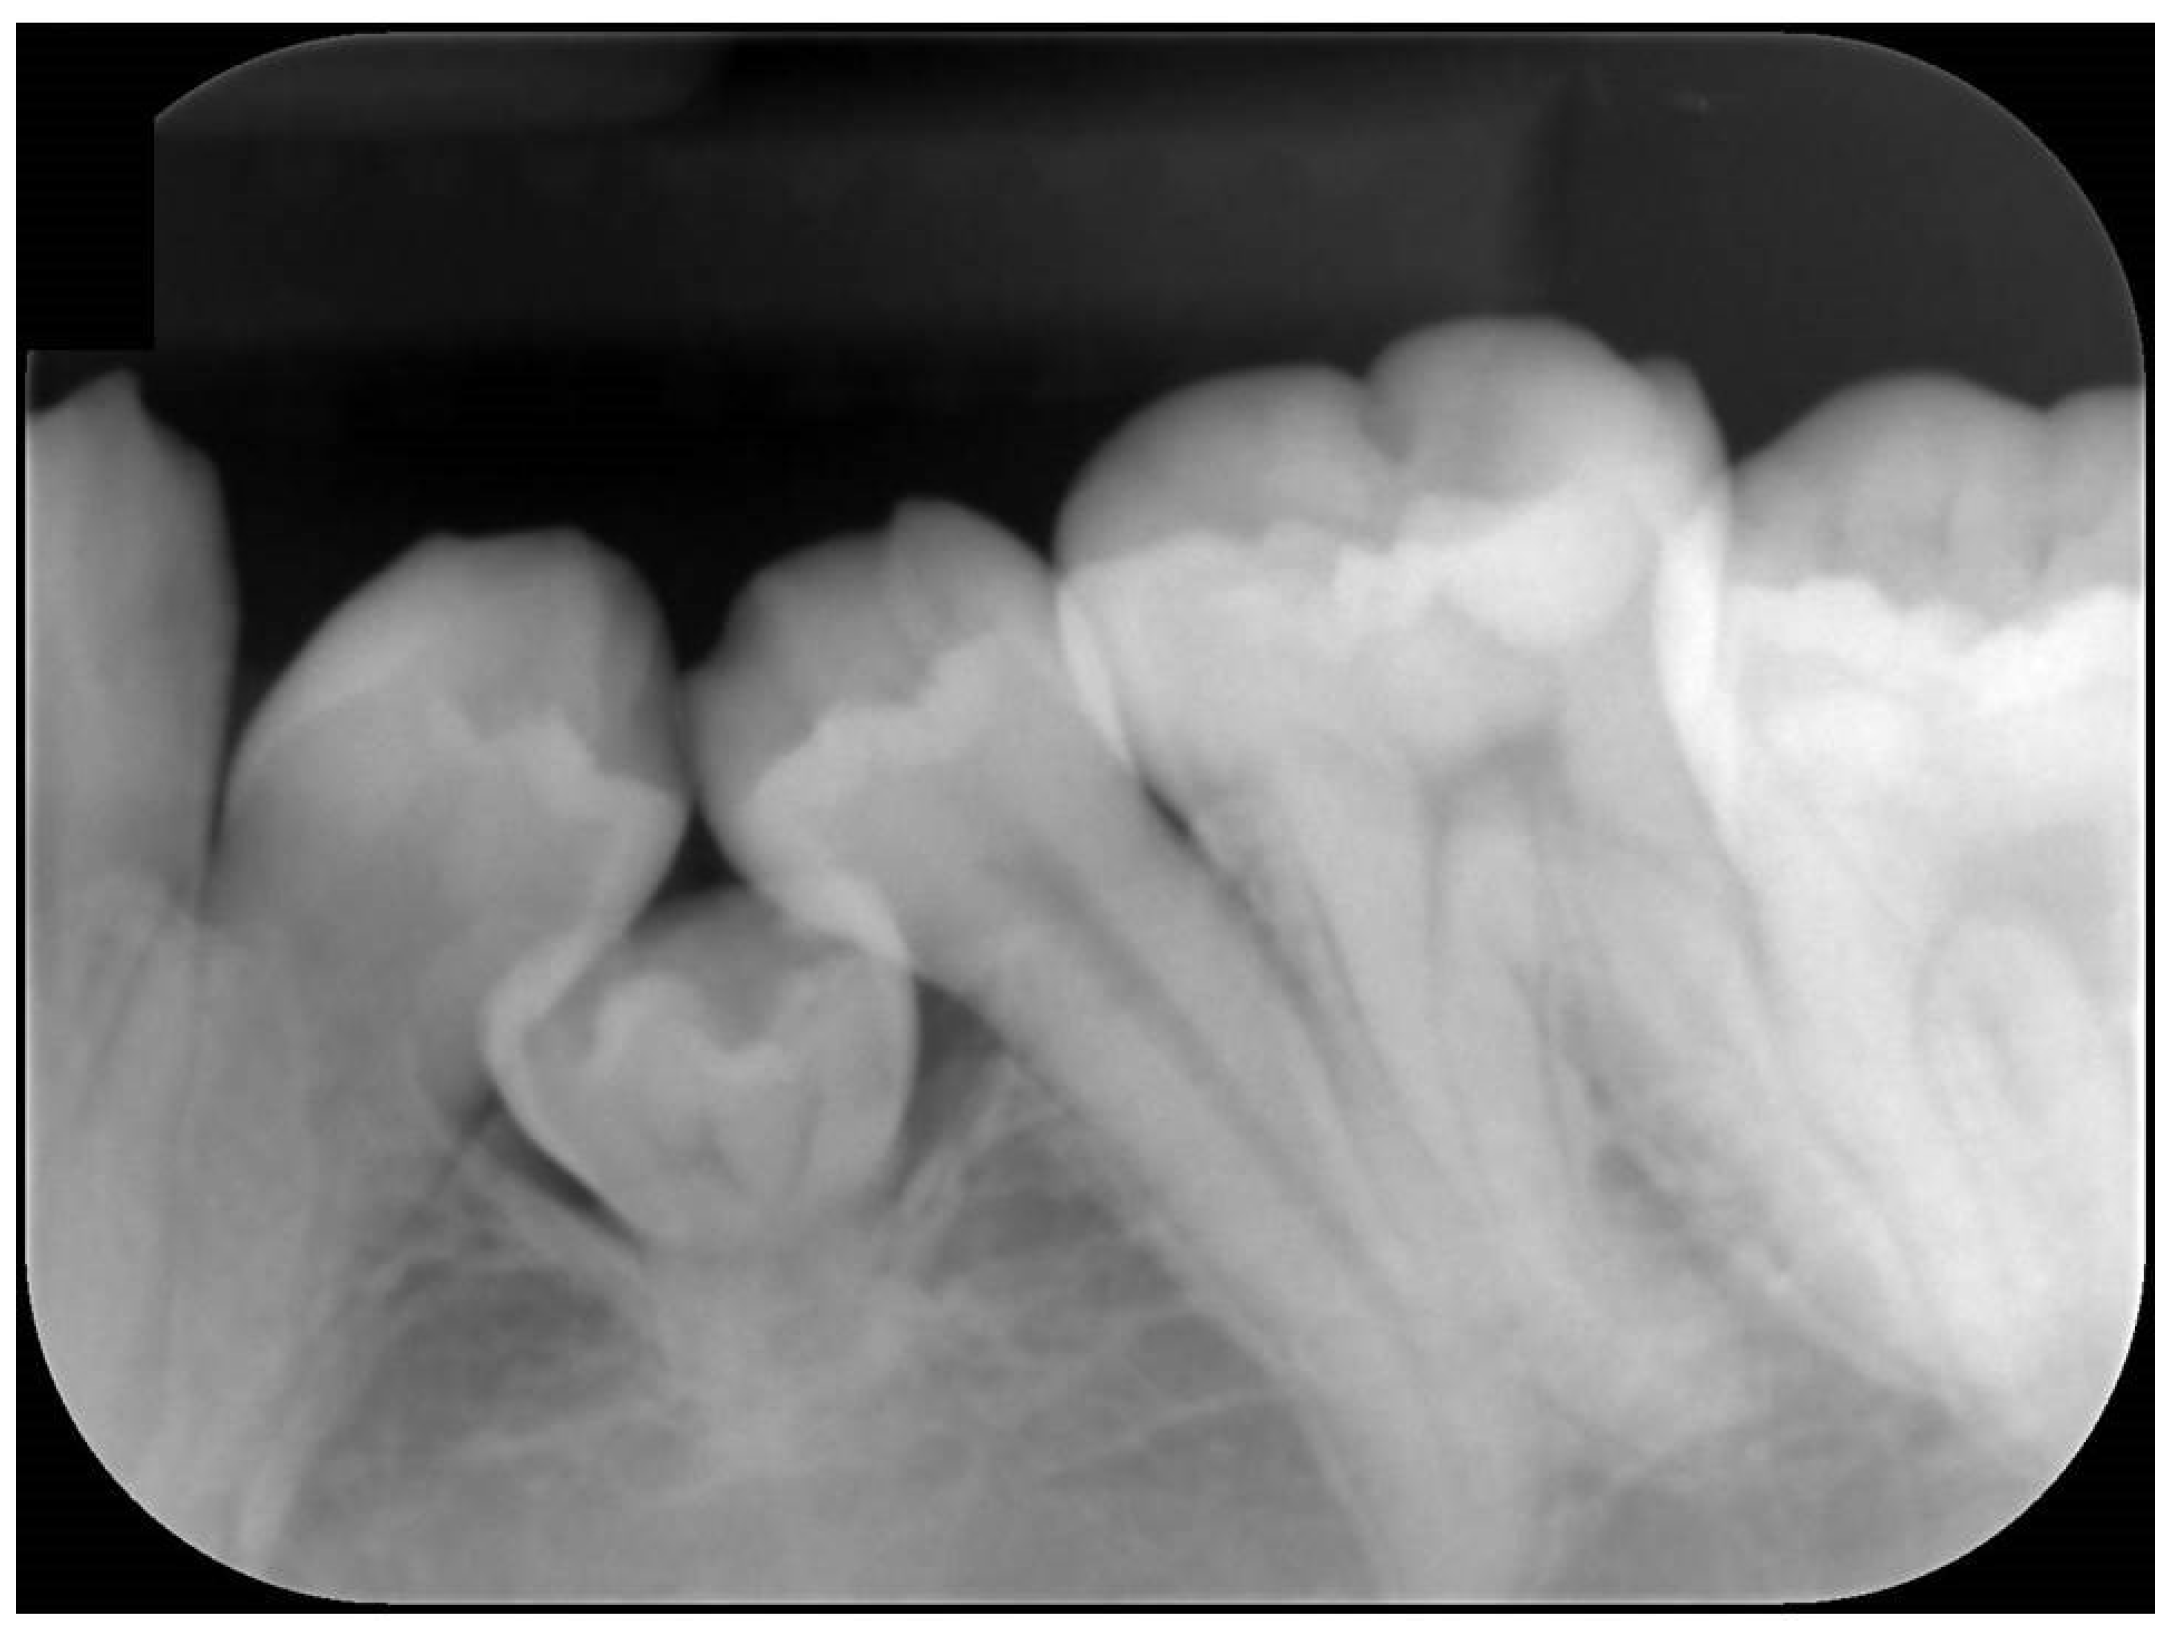

Figure 2.

Dental X-ray image of the left mandibular region of the patient’s mouth, taken under general anesthesia. This revealed hard tissue between the first and second mandibular premolars, which was similar in shape to part of a tooth crown.